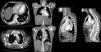

En control tomográfico posterior se identificó zona de reentrada en la arteria ilíaca primitiva izquierda en su tercio proximal, 1cm por debajo de su bifurcación. Se realizó corrección endovascular colocando una extensión ilíaca con endoprótesis TALENT. El paciente permaneció asintomático, pero 4 años después presentó dolor torácico, por lo que se realizó nueva angio-TC, en la que se identificó disección aneurismática de aorta abdominal con el tronco celiaco, arteria mesentérica superior que salía de la luz falsa, y progresión de la disección a la arteria ilíaca derecha (fig. 3).

AngioTC de ingreso caso 2. Stent en cayado aórtico con dilatación aneurismática y trombo intramural concéntrico con un diámetro mayor de 82mm con una luz verdadera de 38mm; disección aneurismática de aorta abdominal con diámetro mayor de 44mm con flap intimal, tronco celiaco que sale de la luz falsa; disección de arteria mesentérica superior; arterias renales que salen de la luz verdadera con progresión de la disección a la ilíaca derecha; stent ilíaco izquierdo permeable.